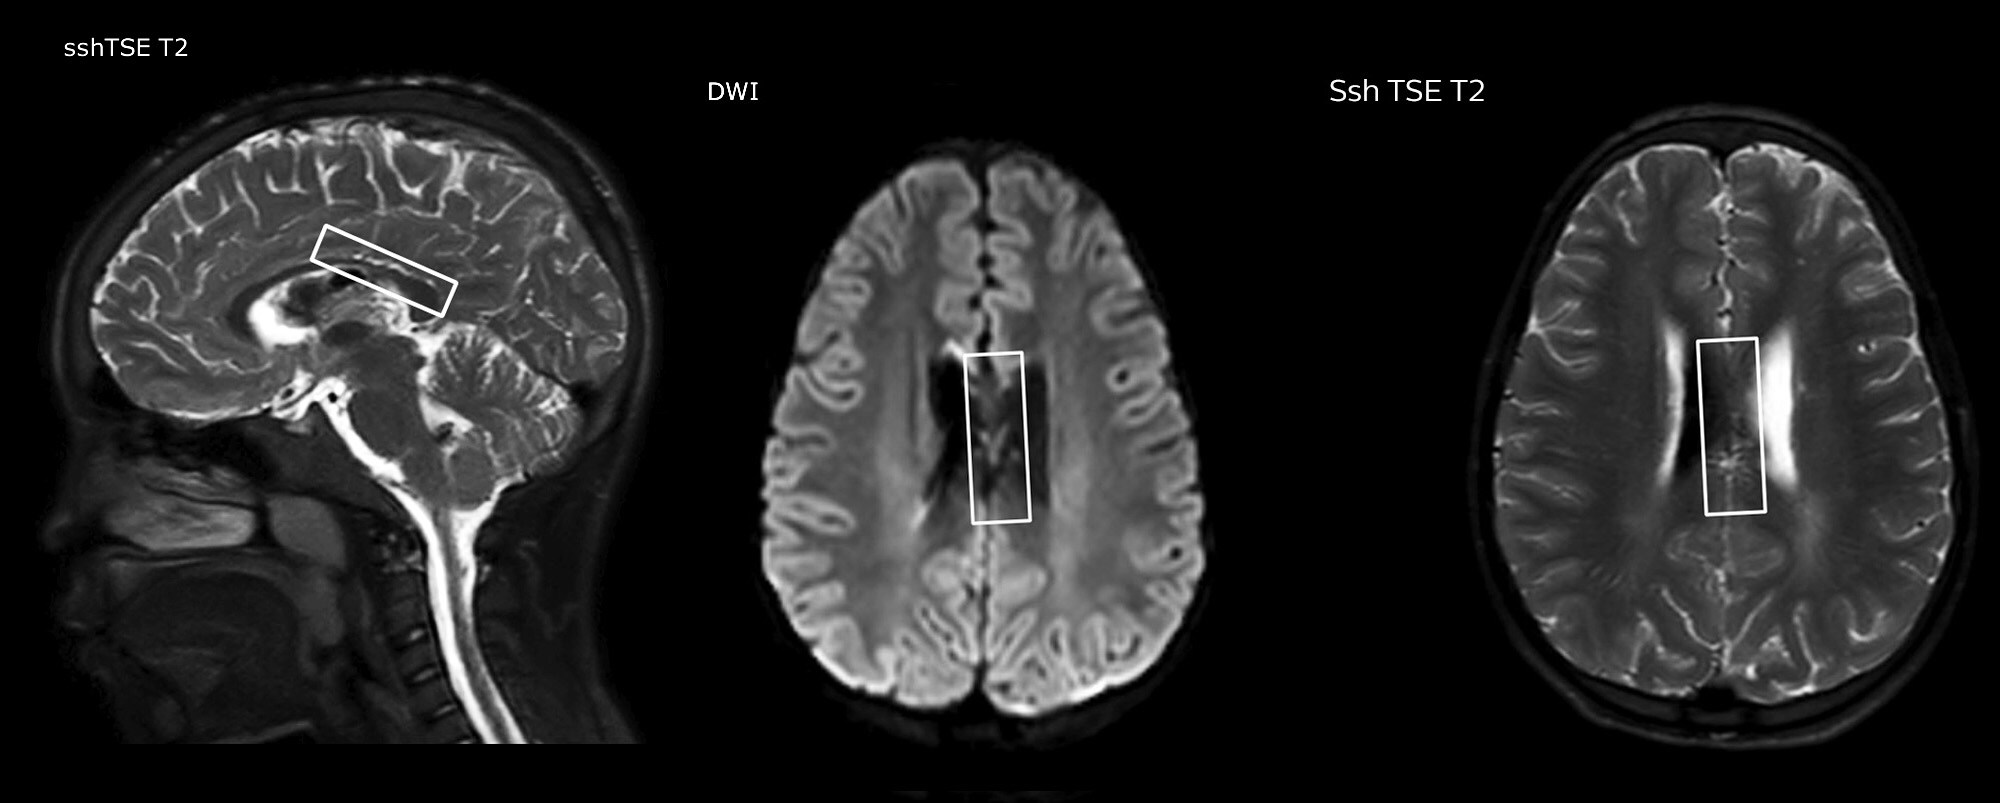

Pseudo-continuous arterial spin labeling (pCASL) was developed for brain perfusion imaging without contrast agent. “This is very desirable in pediatric patients where the general trend is to limit the administration of contrast,” says Dr. Miller. Growing confidence in specific applications “We built up confidence in pCASL by comparing it to contrast-based perfusion imaging. Once we had confidence that it was representing what the contrast perfusions were representing, we increased our diagnostic confidence by serial imaging in either the acute stage or the long term stages in a number of patients with arterial abnormalities.

Dr. Miller uses pCASL for all patients who present with chronic and acute cerebrovascular abnormalities such as acute stroke, as well as patients who present with signs of acute inflammation in the brain, and occasionally in patients with tumors, to assess the perfusion status of their tumor.

“In combination with diffusion weighted imaging, it can help give a more extended assessment of the degree of perfusion abnormality in a patient who is suffering acute ischemia. We have a number of patients who have chronic arterial insufficiency due to prior arterial abnormalities or acquired arterial abnormalities such as sickle cell disease or neurofibromatosis. Sometimes the child’s first manifestation of disease progression is a reduction in brain perfusion before stroke symptoms manifest clinically or in diffusion weighted imaging. We use pCASL to help delineate the perfusion abnormality.”

To other new users I would recommend to also start to interpret the pCASL images in comparison with other standard imaging – T2 and FLAIR and DWI – until the user gains confidence in interpreting these images by themselves.” “A powerful use of pCASL is in patients with chronic cerebrovascular stenosis, where clinicians desire information on how compensatory mechanisms of the brain are performing to enable perfusion to the brain. Often clinicians take into account how the compensatory mechanisms appear to help to provide adequate perfusion to the patient’s brain, and they may intervene surgically or make some other management decision.” “Another special application is the assessment of cerebrovascular reactivity with a Diamox perfusion exam, where we subtract two sets of pCASL images.”

“pCASL has now become more of a first-line scan for assessing perfusion for us, as opposed to DSC-based perfusion imaging with contrast agent. And in patients who were not planned to have contrast, we can perform pCASL for perfusion imaging without need to stop the exam, pull the patient out, and put in an IV. It also negates the postprocessing that’s necessary for dynamic susceptibility contrasts. And it allows us to repeat perfusion imaging in the same patient at the same imaging time, which is helpful in terms of patient motion, or in a situation where a scan needs to be done before pharmacological perfusion imaging.”